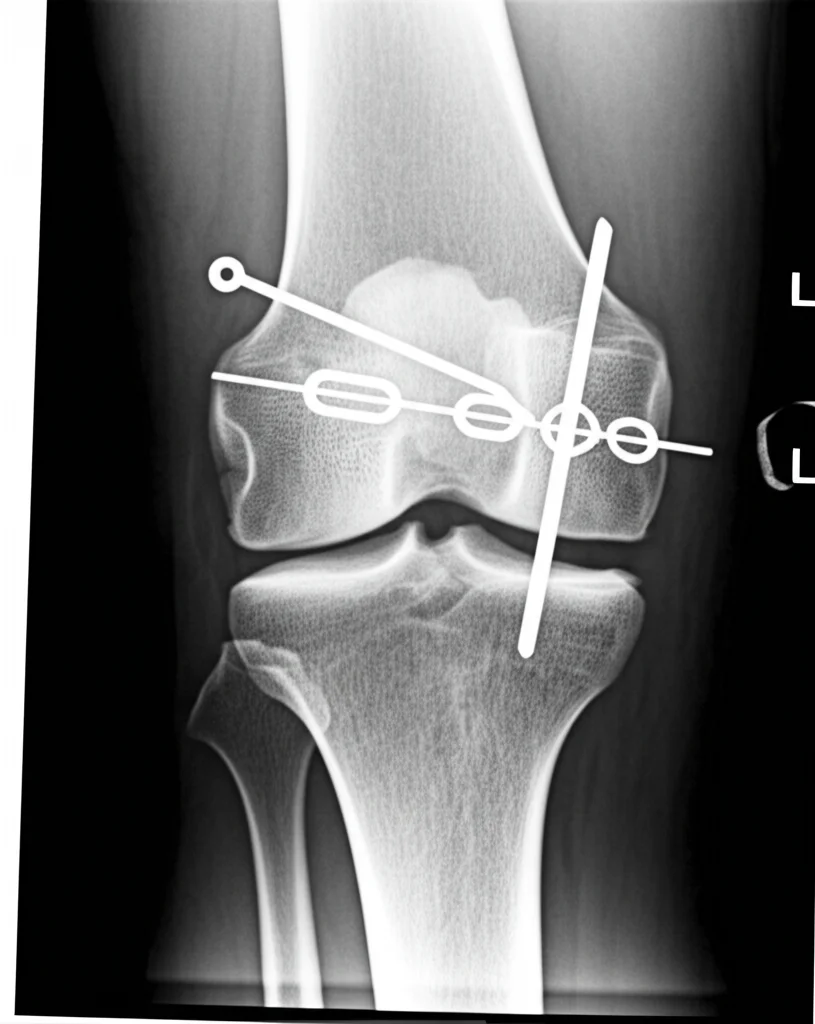

Una Nuova Speranza: Pin Perforati e Cavi Metallici

Con i progressi tecnologici, però, sono arrivati nuovi materiali e nuove idee. Una di queste è l’uso combinato di pin ortopedici perforati e cavi metallici. La ricerca suggeriva che questa combinazione potesse migliorare la compatibilità dei materiali con il corpo, offrire una maggiore stabilità, ridurre l’allentamento e rendere più facile la gestione della frattura.

- Gruppo Osservazione (23 pazienti): Trattati con la nuova tecnica, usando pin ortopedici perforati (da 2.0 mm, in lega di titanio) e cavi metallici (da 1.3 mm, sempre in titanio).

- Gruppo Controllo (22 pazienti): Trattati con il metodo standard AO, usando fili di Kirschner (da 2.0 mm) e fili d’acciaio (da 1.2 mm).

L’intervento con i pin perforati è concettualmente simile a quello AO, ma con alcune differenze chiave. Dopo aver esposto e ridotto la frattura, si inseriscono due pin perforati paralleli, perpendicolari alla linea di frattura. Poi si fa passare il cavo metallico attraverso i fori dei pin, creando una configurazione a “figura di otto” sulla parte anteriore della rotula. Si tende il cavo e lo si blocca con una fibbia specifica. Si verifica la stabilità e si sutura.